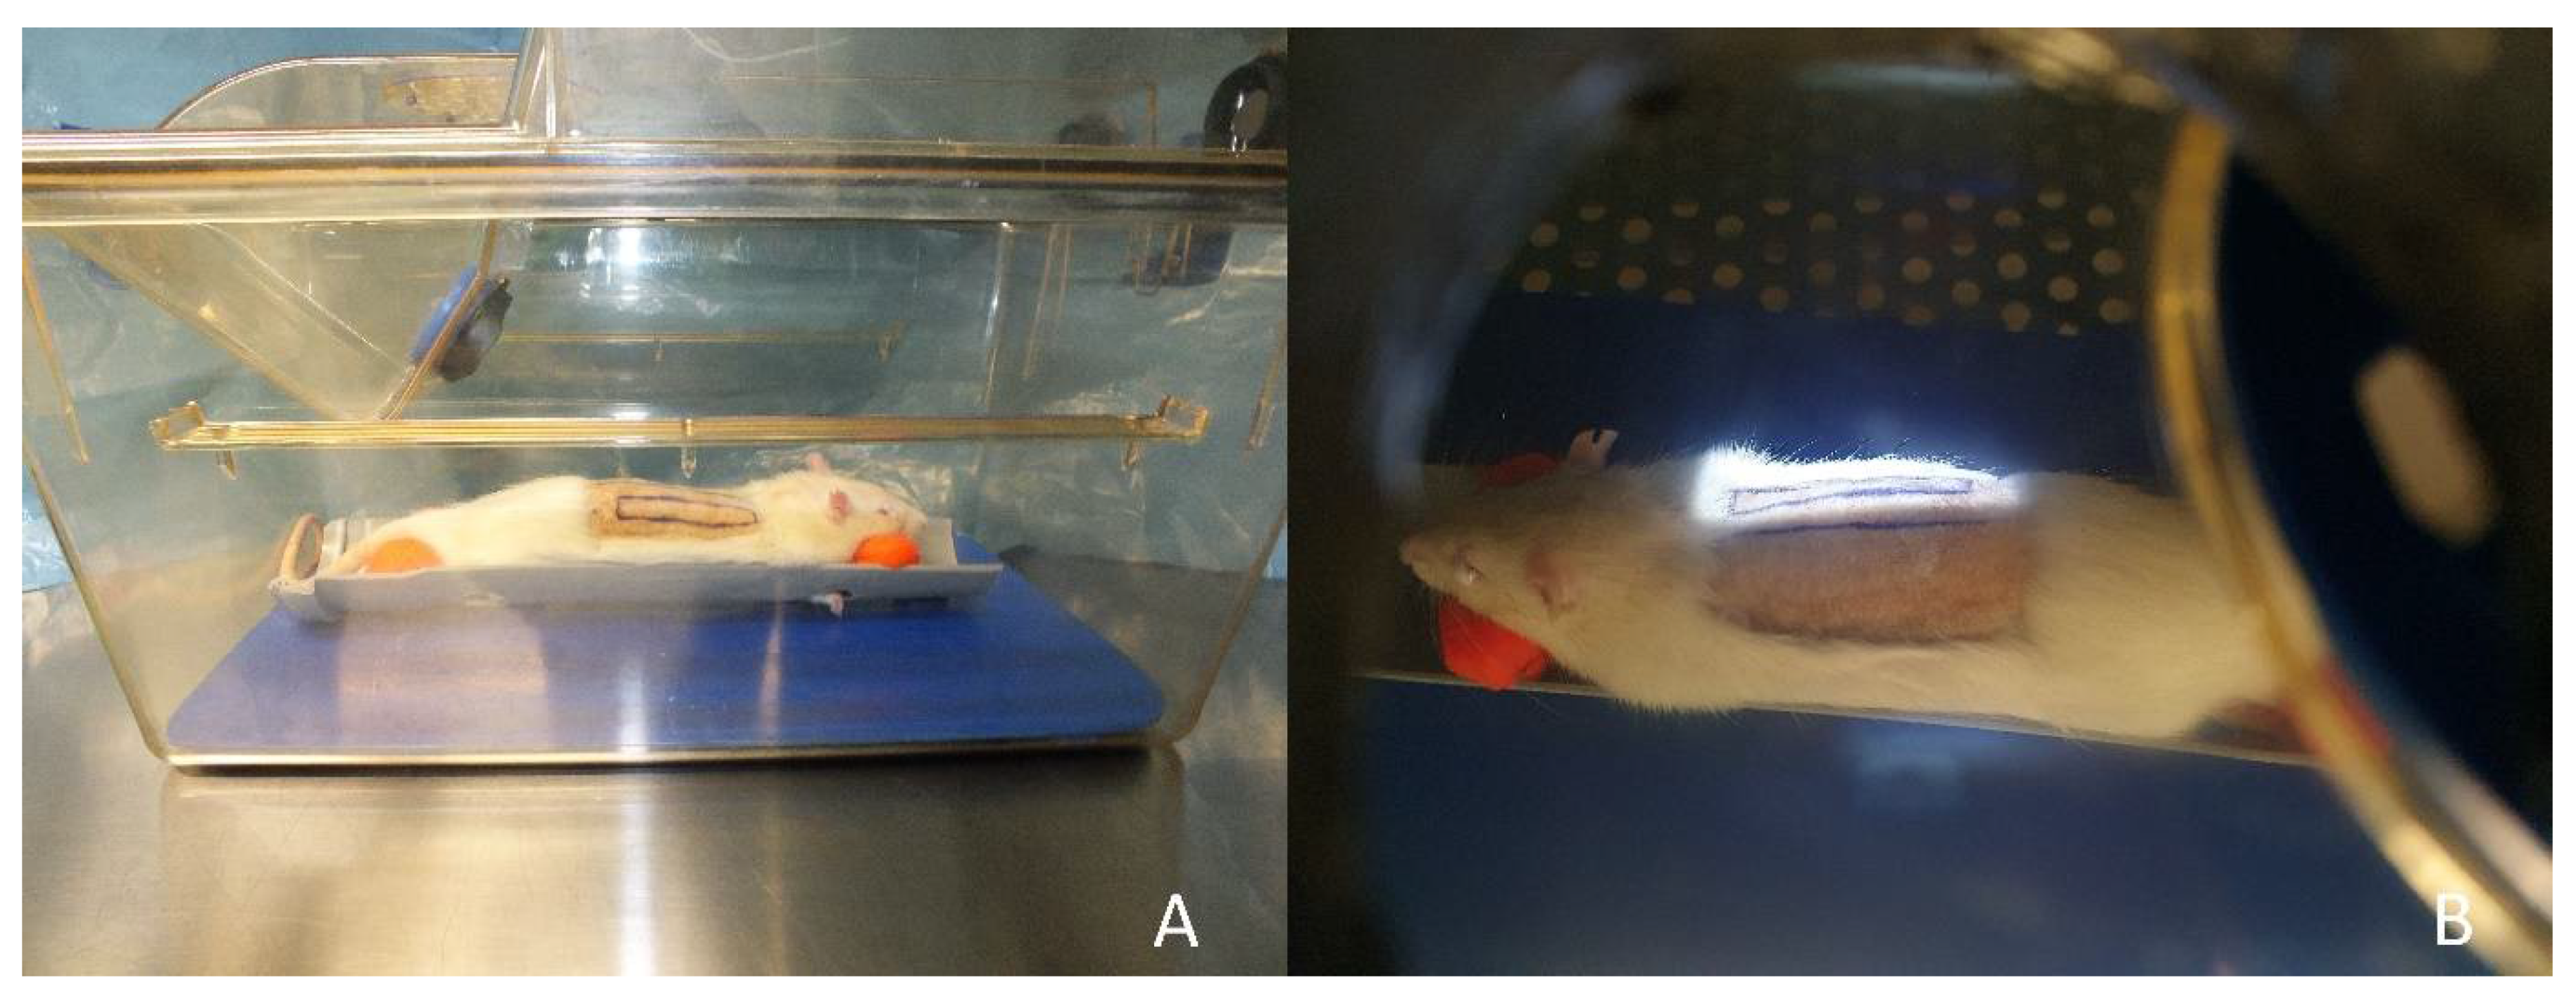

2.1. Surgical Procedure

2.2. Irradiation Procedure

2.3. Groups

2.4. Imaging